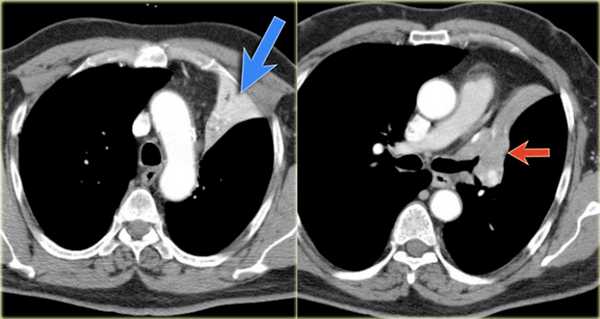

- Минимальное уменьшение объема легкого без подъема левого купола диафрагма.

- В загрудинном пространстве визуализируются изменения высокой плотности, которые спавшейся верхней доли левого легкого.

- Корень левого легкого патологичен, что может соответствовать образованию, обтурирующее просвет бронха.

- Выше перечисленные находки наводят на мысль, что это ателектаз верхней доли левого легкого.

На КТ снимках синей стрелкой указан долевой ателектаз, а красной стрелкой опухоль, которая обтурирует левый верхний долевой бронх (центральный рак легкого.